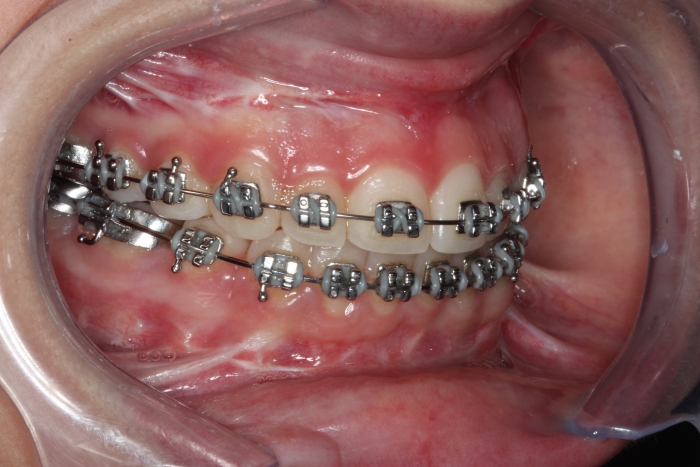

Mordida inicial

Mordida após a cirurgia